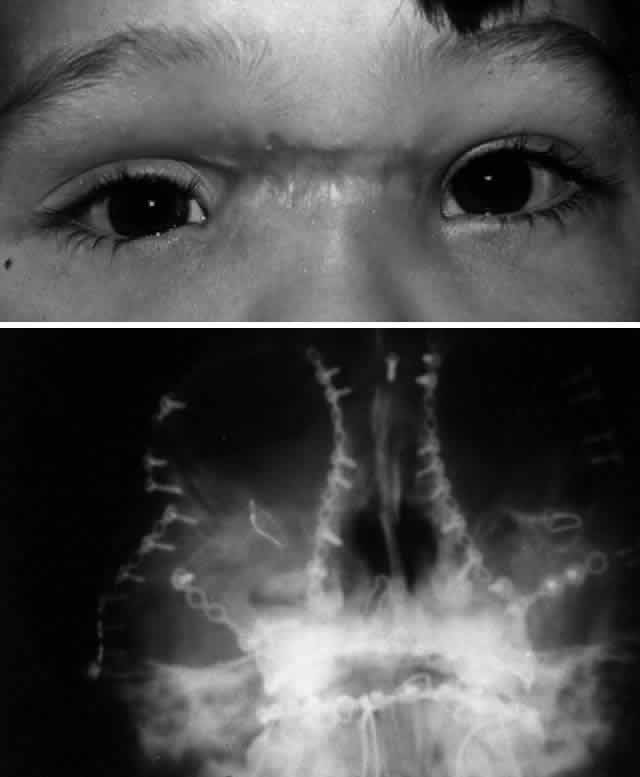

MEDIAL ORBITAL RIM (NASOETHMOID-ORBITAL REGION). The bones of the medial orbital rim represent the lateral aspect of the nasoethmoid complex, and fractures of the medial orbital rim are most typically the component of a more generalized nasoethmoid orbital injury. Nasoethmoid orbital fractures may be isolated or associated with other more extensive craniofacial fractures (e.g., Le Fort II and III). Successful management of nasoethmoid orbital injury requires consideration of both the bony and soft tissue injury.38,39,45–47 The most important soft tissue structure in the nasoethmoid-orbital region is the medial canthal tendon. The medial canthal tendon has medial and posterior insertions to the anterior and posterior lacrimal crest in the anterior portion of the medial orbit.16 Disruption of the medial canthal tendon or the bony segment containing the insertion of the medial canthal tendon can result in telecanthus. Because the lacrimal drainage system is closely tied with this area, it is at risk for injury from the original trauma as well as during surgical repair.

Nasoethmoid orbital injuries may also be associated with fracture extension into the anterior cranial fossa (adjacent to the cribriform plate), which may result in cerebrospinal fluid rhinorrhea, pneumocephalus, olfactory nerve disruption, and potential frontal lobe injury. Markowitz and colleagues45 have proposed a classification scheme for nasoethmoid orbital fractures that is related to the condition and position of what they term the central fragment (the portion of the frontal process of the maxilla providing the bony insertion of the medial canthal tendon). Three types of fractures are outlined:

Type 2 fractures, because of bony comminution, generally require transnasal wiring to stabilize the central fracture segment containing the medial canthal tendon and to minimize the risk of postoperative telecanthus. The canthal tendon-bearing portion of the central fragment is isolated by subperiosteal dissection, except for the area of medial canthal tendon insertion, which is not detached. Transnasal (28-gauge) wires are passed through drill holes placed superior and posterior to the lacrimal fossa (and medial canthal tendon) and on the central fragment. These wires are then passed across the nose in a trans-septal fashion. If a bilateral nasoethmoid fracture is present, the two central fragments can be linked together. With unilateral fractures, the transnasal wire extends to the intact contralateral nasal dorsal bone. All other nasal and orbital bone segments are first linked by wires and then fixed to the frontal bone and inferior orbital rim/maxillary buttress with junctional plate and screw fixation. Tightening of the transnasal wires produces central fragment reduction and creates proper intercanthal dimensions. The intercanthal soft tissue distance is rarely overcorrected, and it is more frequently undercorrected. Therefore, transnasal reduction should deliberately minimize the bony interorbital distance between the medial orbital rims to obtain a satisfactory result.

Type 3 comminuted fractures rarely avulse the medial canthal tendon; however, the central fragment is frequently too small in such fractures to utilize in reconstruction. In such cases, the medial canthal tendon is detached and transnasal reduction of the medial orbital rim segments is performed, followed by direct transnasal wiring of the medial canthal tendon itself. The medial canthal tendon may be attached to the transnasal wire with a smaller permanent monofilament or braided suture. It is important to pass the transnasal wire posterior and slightly superior to the lacrimal sac fossa in order to achieve proper eyelid-globe apposition and impart a natural appearance to the medial canthus. Care should be taken to preserve the lacrimal system during transnasal wiring; this can be facilitated by placement of lacrimal probes within the canaliculi.

Other techniques for securing the medial canthal tendon in the setting of nasoethmoid orbital fractures have been described. Shore and associates47 described repair of telecanthus using a miniplate cantilevered from the lateral aspect of the nose and directed posteriorly into the orbit to provide a stable fixation point for the medial canthal tendon. This technique is probably most applicable for cases of unilateral traumatic telecanthus, in which poor bony support for transnasal wires is suggested on preoperative CT. After fracture reduction with transnasal wiring or medial canthal tendon fixation, soft padded nasal bolsters may be placed to help minimize edema and hematoma as well as to adapt the skin to the nasal bones. Although these external bolsters play no role in the reduction or stabilization of the medial orbital rims, some authors believe they may help mold the bones of the nose and may minimize the scarring and thickening of the medial canthal tissues. These bolsters are secured with an additional transnasal wire, which is removed 7 to 10 days after surgery. Adequate aesthetic repair of extensive fractures in this region can be challenging.